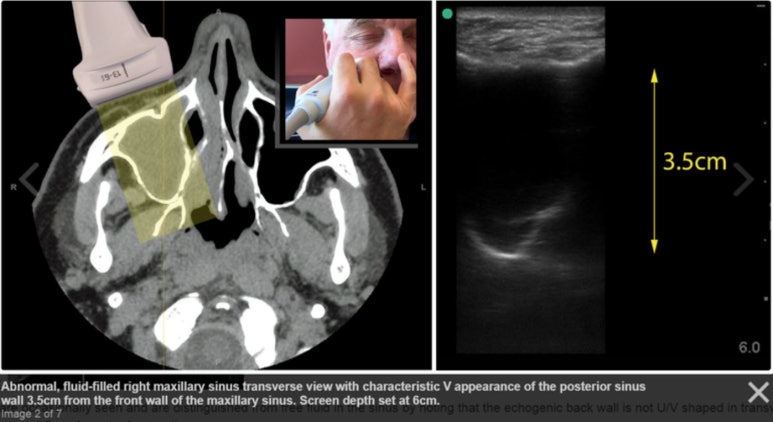

부비동 초음파 검사를 의뢰한 결과

아래 그림처럼

부비동에 농이 많이 차있어

염증이 있는 상태였습니다.